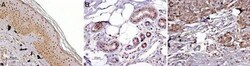

Supportive validation

- Submitted by

- Invitrogen Antibodies (provider)

- Main image

- Experimental details

- Expressionof MC1R in normal skin and melanoma - Immunohistochemical staining of paraffin embeddednormal skin and melanoma sections using Anti-MC1 Receptor Antibody (#AMR-020) (1:100).MCR1 staining (red-brown color is highly specificin A. epidermal cells, B. eccrine sweat gland cells and C. melanoma cells. Color reaction was obtained with DAB. Hematoxilin is used as the counterstain.